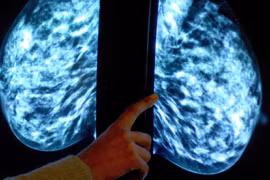

(Kiến Thức) - Có mối liên hệ giữa ung thư vú và làm việc theo ca với chất melatonin (chất chống oxi hóa, chống viêm, tăng cường hệ miễn dịch và ngăn ngừa ung thư).